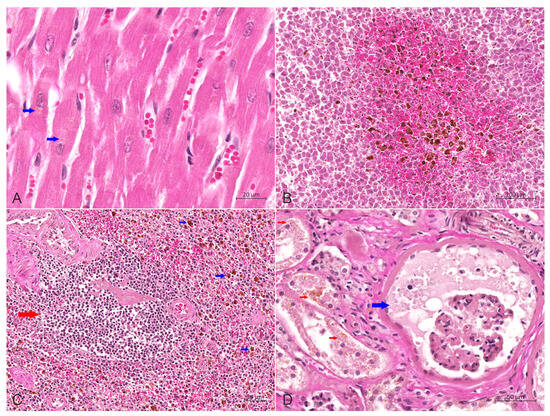

Background: Feline pulmonary Langerhans cells histiocytosis (PLCH) is a rare disorder that results in progressive respiratory failure secondary to pulmonary parenchymal infiltration with Langerhans cells (LCs). A diagnosis of PLCH is proposed based on the clinical features and pathological findings and confirmed based [...] Read more.

Background: Feline pulmonary Langerhans cells histiocytosis (PLCH) is a rare disorder that results in progressive respiratory failure secondary to pulmonary parenchymal infiltration with Langerhans cells (LCs). A diagnosis of PLCH is proposed based on the clinical features and pathological findings and confirmed based on the infiltrating histiocytic cells. There are few documented cases of feline PLCH, and this case report of PLCH in an African Lion could present new information and aspects of this feline histiocytic disease. Case presentation: An African lion at Hohhot Zoo showing severe hyporexia and dyspnea with subsequent mental depression and emaciation died of exhaustion after a 35-day course of illness. Empirical treatment did not have a significant effect. An autopsy revealed that the lungs were enlarged and hardened due to infiltrative lesions, with many yellowish-white foci in all the lobes and sections. Furthermore, the kidneys were atrophied and had scattered grayish-white lesions on the surface. At the same time, congestion was widely distributed in various locations, including the liver, subcutaneous loose connective tissues, serosal surface and other tissues and organs. Histologically, proliferative histiocytic cells (PHCs) were scattered in the alveolar cavities, bronchioles and submucosa of bronchioles, with evident cellular and nuclear pleomorphism, and thus the alveolar septa were obliterated. The histopathological changes in other organs included chronic sclerosing glomerulonephritis, proliferated Kupffer cells in the liver, adrenal edema and interstitial connective tissue hyperplasia, as well as atrophy of the small intestines and spleen. Furthermore, immunohistochemical analysis results were strongly positive for CD1a, vimentin, S100 and E-cadherin in the membrane or cytoplasm of PHCs, supporting an LC phenotype. Conclusions: Here, we present a rare pulmonary Langerhans cell histiocytosis case in an African lion. Full article